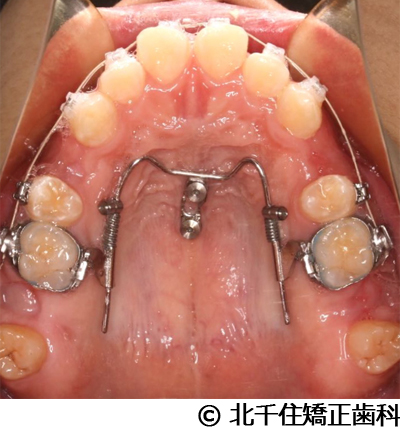

【症例2】上顎前突症

- 治療前

- 治療中

- 治療後

- 治療名

- 上顎前突症

- 費用

- 1,399,000円(税込)

- 期間

- 3年6ヵ月

- 治療回数

- 42回

- 通院頻度

- 1ヵ月ごと

- 年齢・性別

- 19歳10ヵ月・男性(初診時)

治療内容

主訴:出っ歯、口元の突出、横顔をきれいにしたい

治療方法

骨格性の上顎前突、上下顎第一小臼歯4本及び上顎第二大臼歯を抜歯して矯正用アンカースクリューを併用してワイヤー矯正治療(セラミックブラケット)。

治療結果

骨格性上顎前突に対し、抜歯および矯正用アンカースクリューを併用した矯正治療により歯列および咬合関係の調整を行った症例である。治療後は保定装置を使用し、歯列および咬合の安定維持を目的として定期的な経過観察を行っている。

※治療結果は個人差があります。

治療を行う上での注意点(リスク・副作用)

歯磨き不良に伴うカリエスや歯周病、顎関節症、歯根吸収など。